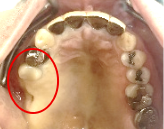

Before

※赤丸は、歯根が破折していたため抜歯しました

※黄色丸は、2006年10月に埋入したインプラント

After

※緑丸は、今回埋入したインプラント